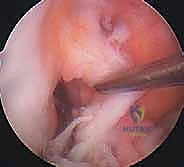

تقنيات جراحة إعادة بناء الرباط الصليبي الأمامي وأنواع الطعوم

لا يمكن خياطة الرباط الصليبي الأمامي المتمزق (إلا في حالات نادرة جداً لتمزقات معينة عند نقطة الاتصال العظمي). لذلك، يجب "إعادة بناء" (Reconstruction) الرباط باستخدام نسيج بديل يُسمى "الطعم" (Graft).

الخطوة الأولى: الفحص بالمنظار الجراحي 4K

يستخدم الدكتور